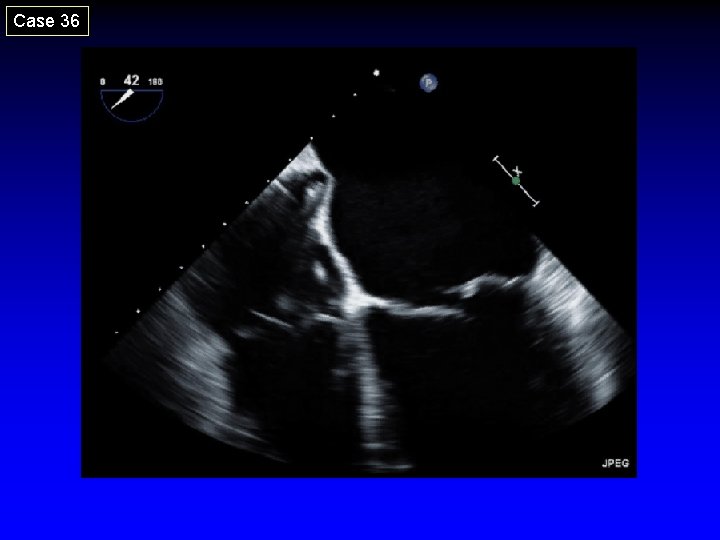

Case 36